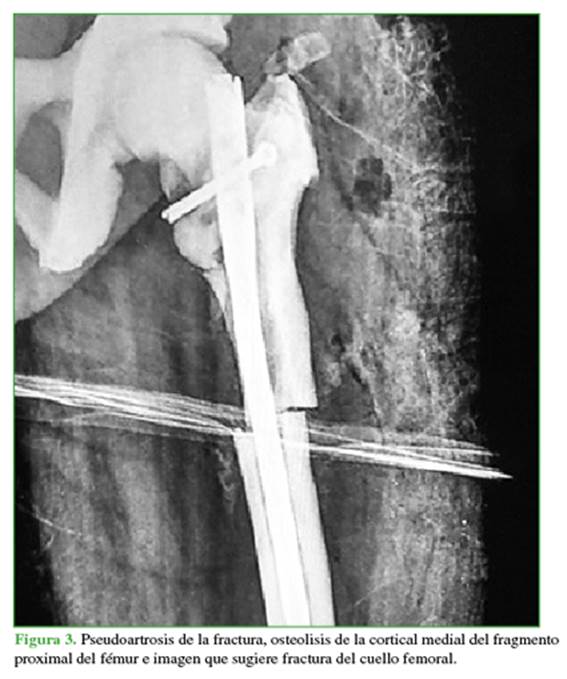

Durante la evolución posoperatoria por la presencia de pseudoartrosis (diagnosticada a los 6 meses de la operación y manejada en otra institución), se realiza retiro de material de osteosíntesis (clavo intramedular bloqueado) y resección de la cabeza femoral, por lo que queda en artroplastia de resección (Figuras 3 y 4).

Mujer de 63 años, residente en la ciudad de Medellín, Colombia. Se trataba de una trabajadora independiente con diagnóstico previo de enfermedad de Paget de presentación poliostótica e historia familiar de enfermedad de Paget, diagnosticada de forma incidental por los hallazgos radiológicos y el antecedente familiar. En 2015, la paciente sufre una caída desde su propia altura y se comprueba fractura subtrocantérica de cadera izquierda, a la cual se le dio manejo quirúrgico en otra institución. Se considera que la fractura se presentó en hueso previamente patológico y comprometido por la enfermedad de Paget (Figuras 1 y 2).